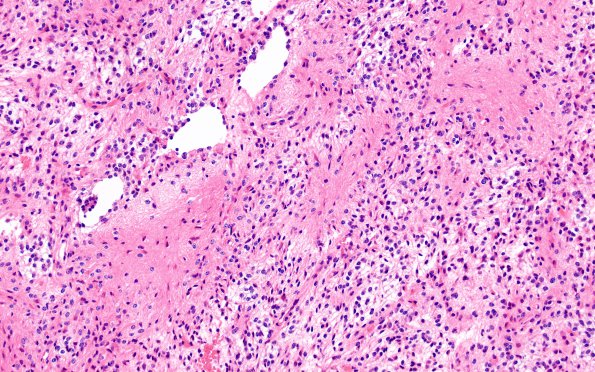

Astrocytoma, pilocytic - Microscopic

1B1 Astrocytoma, pilocytic (Case 1) H&E 6

A low magnification image shows a biphasic fibrillary and microcystic pattern (H&E)